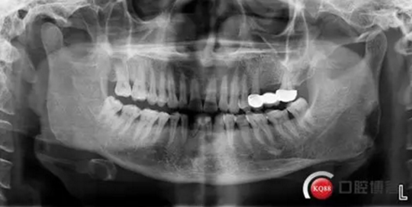

患者,男性,47歲,全身情況良好,無手術禁忌,口內(nèi)因下前牙缺損松動不美觀來院。初診檢查時發(fā)現(xiàn)患者前牙深覆合,下頜32、42缺失。31、41松動二度,切緣磨耗嚴重,可探及髓腔,無保留價值。X-RAY檢查顯示:下頜前牙區(qū)寬度狹窄,咬合空間不足,無法行常規(guī)種植修復.

下圖是術前資料